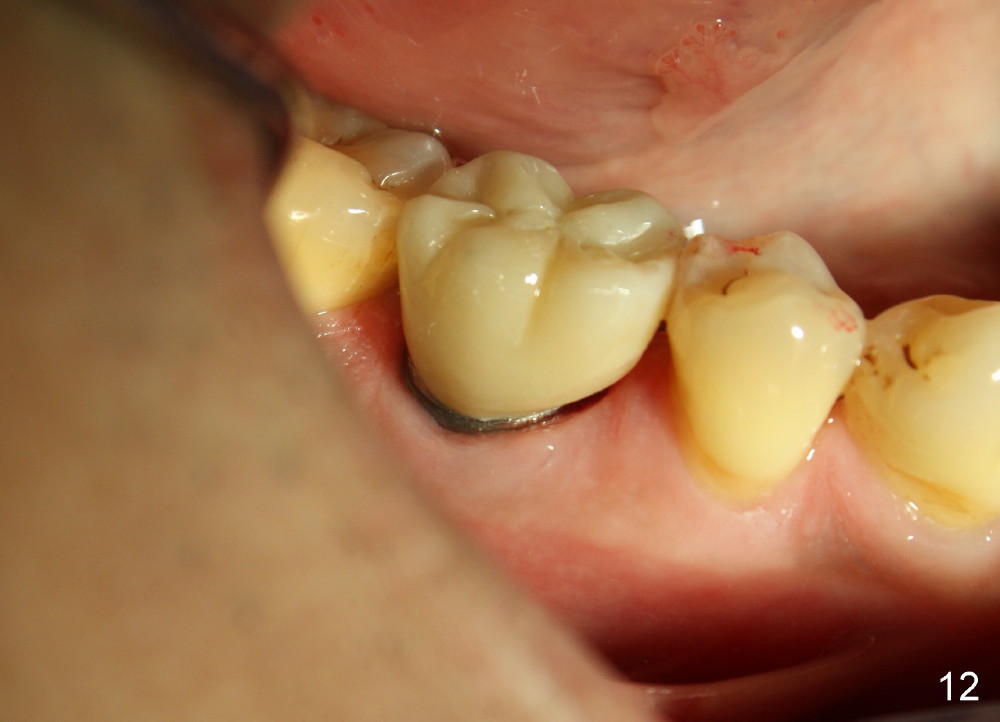

The distal socket is closed completely with suture, whereas the mesiobuccal space is partially closed with collagen gauze and suture (Fig.8 *). The wound is then covered by perio dressing. The gingiva heals around the implant 18 days postop (Fig.9). Three months postop, the implant is stable. The mesial upper portion of the threads appears to have better contact with the bone (Fig.10 <, as compared to Fig.7); the density of the distal socket seems to increase (*). There is no buccal plate atrophy (Fig.11 ^). Supragingival margin is designed for the crown to prevent periimplantitis (Fig.12)